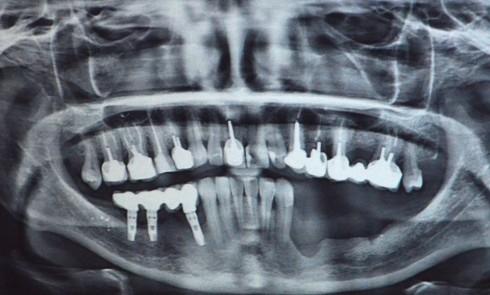

Parodontologie